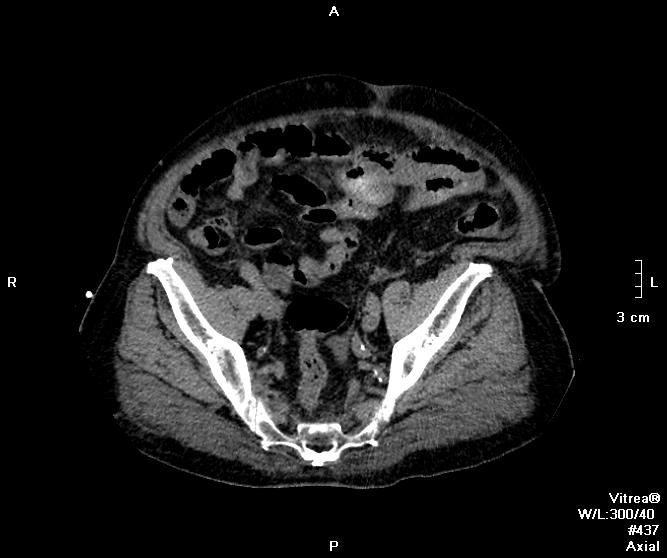

Пациент оперирован по поводу аденоКа толстого кишечника, гемиколэктомия. Онкопоиск, поиск вторичного поражения.

В воротах печени беда, но не об этом сейчас. Прицельно смотрим контраст.

Артериальная.

Венозная.

отсроченные

Во втором случае наблюдается гиподенсный участок в печени.

дифференцируем между метастазом и холангиокарциномой

Случай 2. Опять не попали в фазы, рано. Исследование малоинформативно по сути(. Какова скорость введения автошприцем? Катетер кубитальный или в запястье?